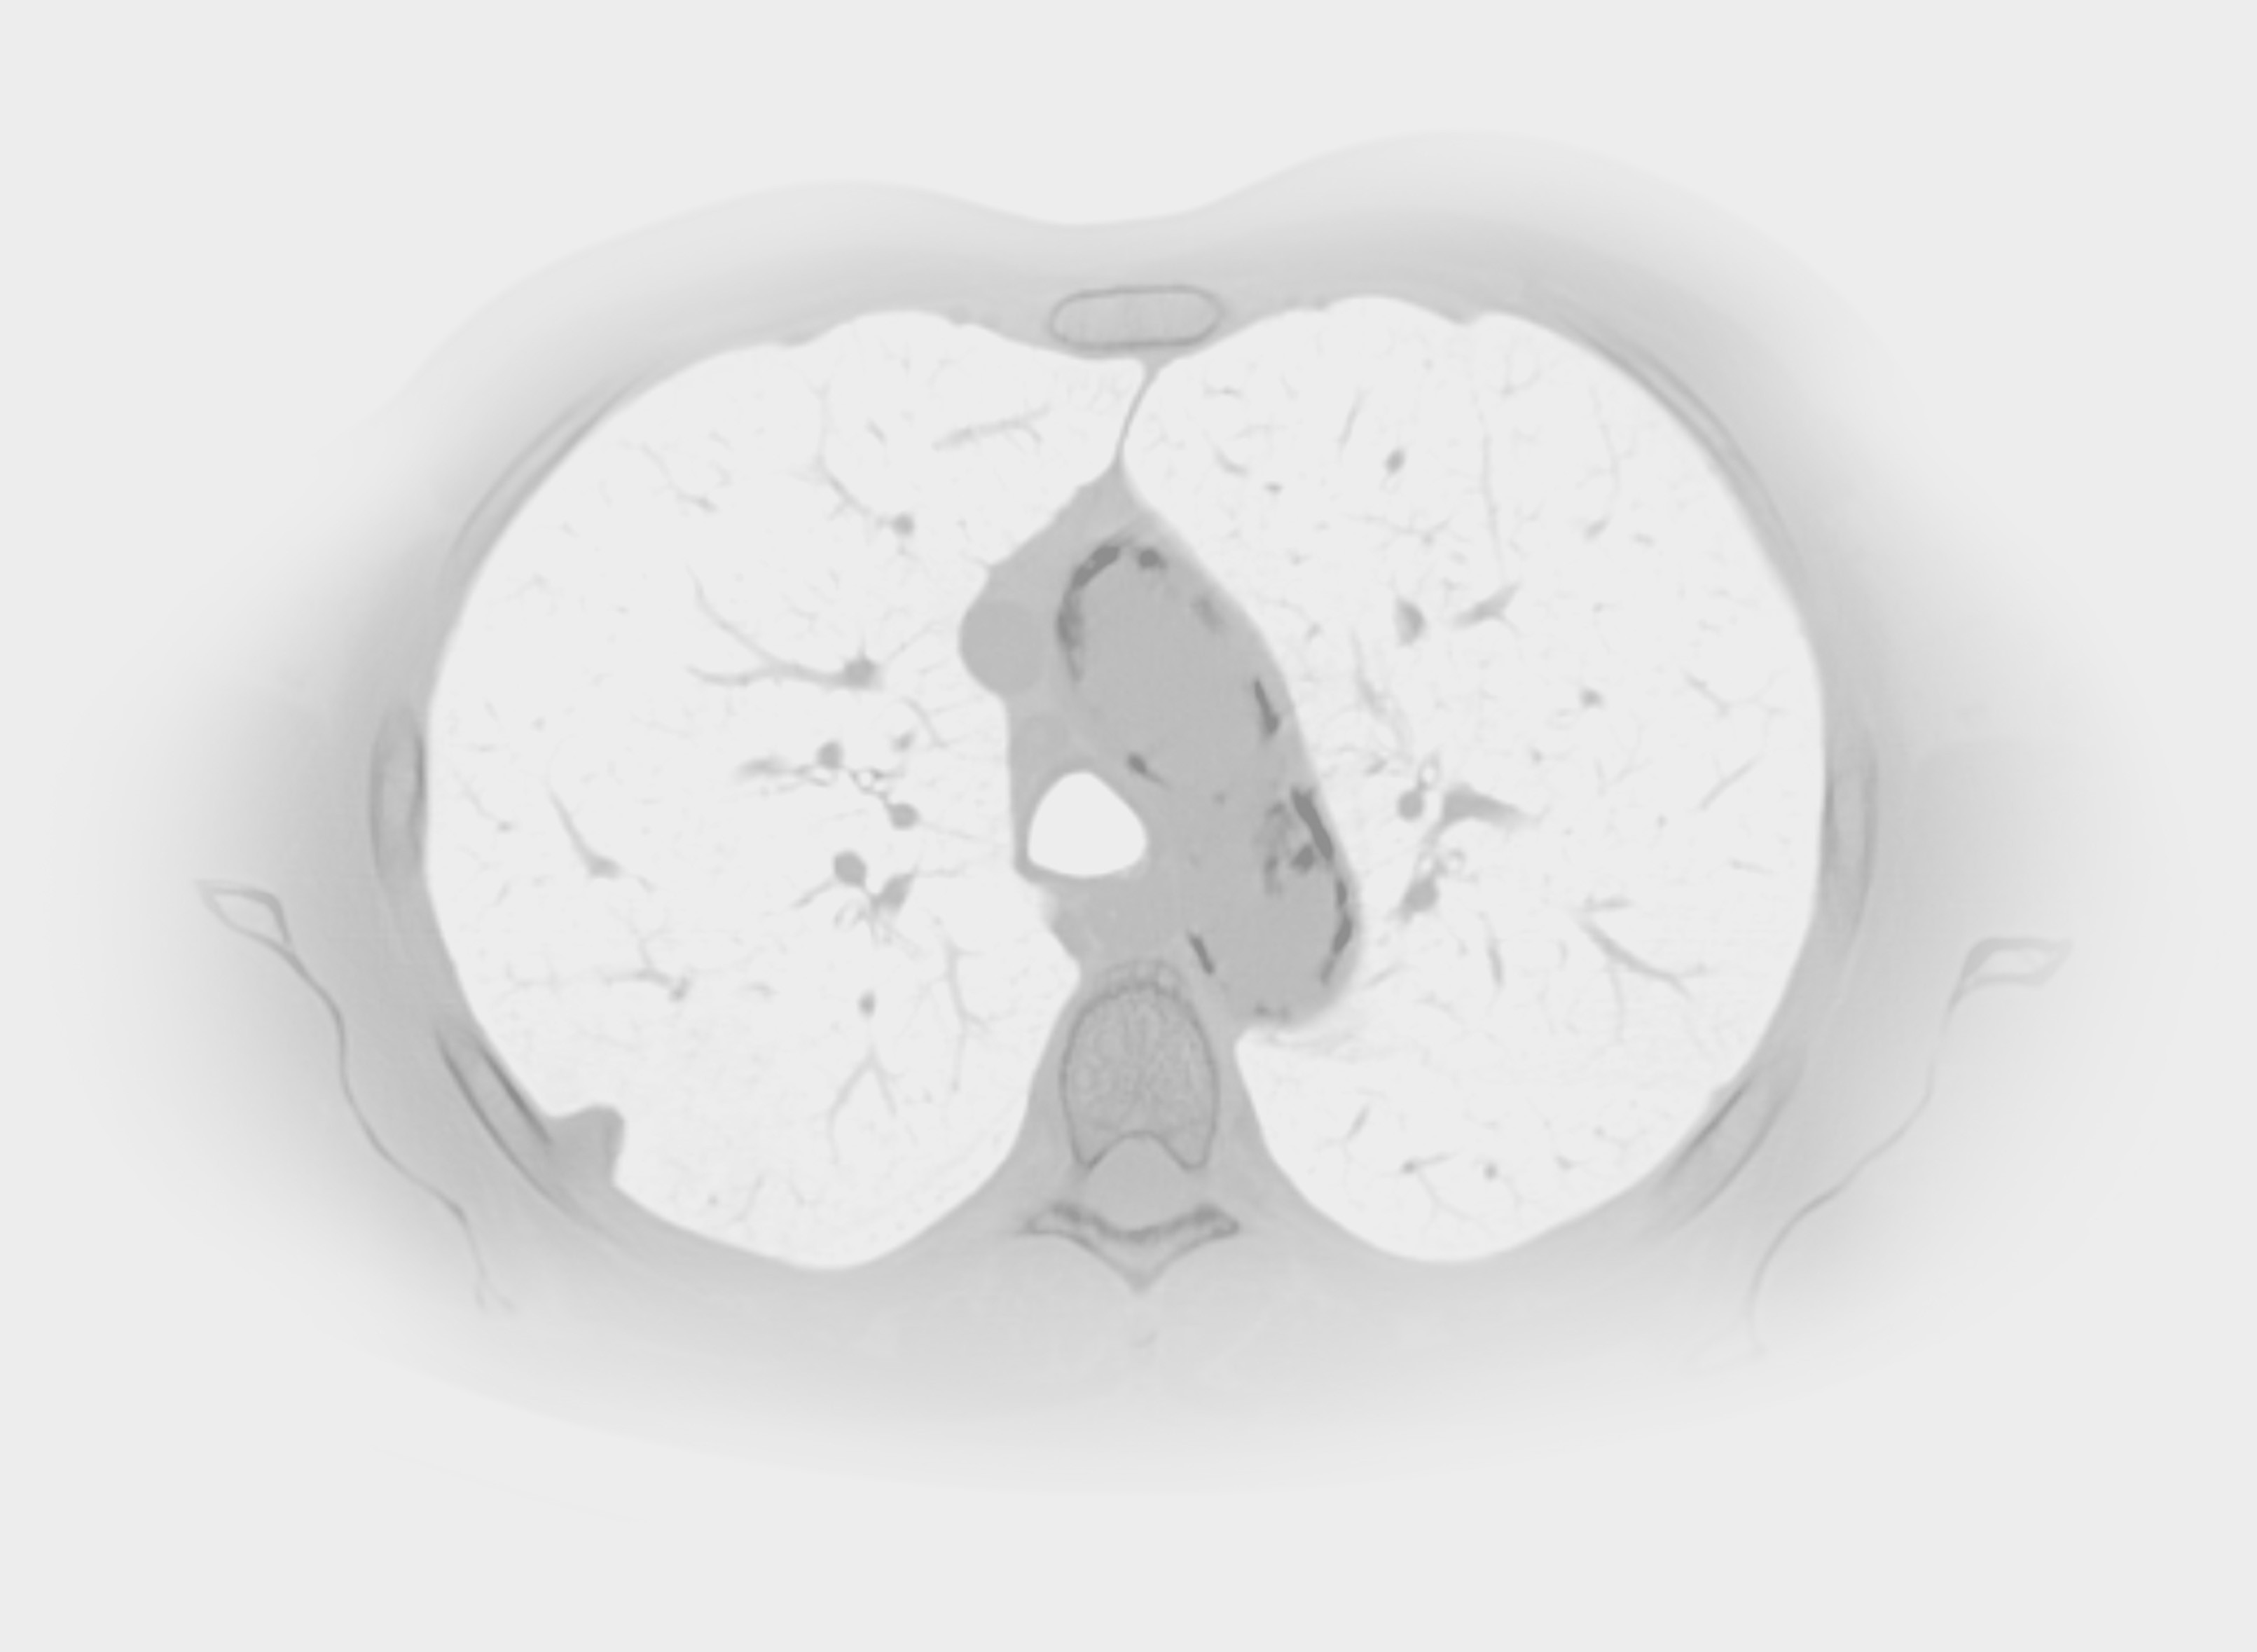

How it looks in practice

See how Carebot works in practice. Compare the image with AI and without AI.

Without Carebot

With Carebot